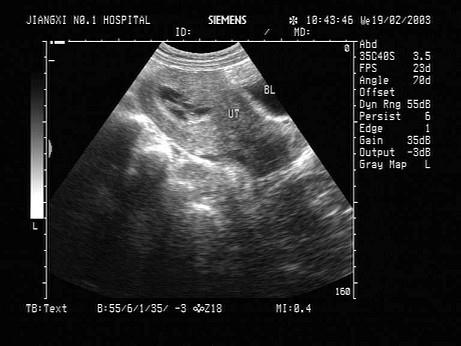

问题 女性,27岁,药物流产术后13天,阴道仍有出血。超声检查如图,最可能的诊断为?(?)

选项 A.子宫肌瘤 B.葡萄胎 C.宫腔残留 D.附件炎性包块 E.宫腔积液

答案 C